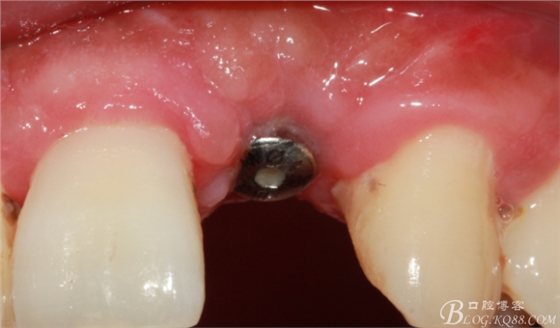

4個(gè)月后,唇側(cè)豐滿度尚可,與鄰牙之間齦乳頭完整。

保留齦乳頭翻小瓣。

翻開后驚喜的發(fā)現(xiàn),術(shù)區(qū)成骨非常好,去除部分骨才暴露那顆長鈦釘。